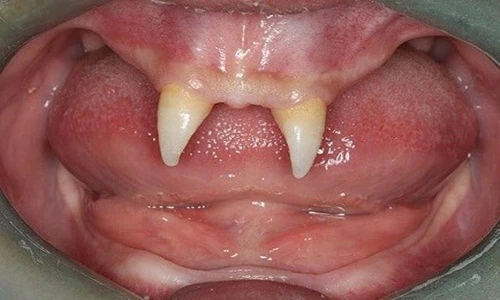

Một cậu bé người Trung Quốc mọc duy nhất 2 chiếc răng năng nhọn hoắt giống hệt ma cà rồng. Ảnh; Sina.

Nguyên nhân chiếc răng ma cà rồng mọc trong miệng cậu bé này chính là do mắc phải một căn bệnh lạ hiếm gặp.